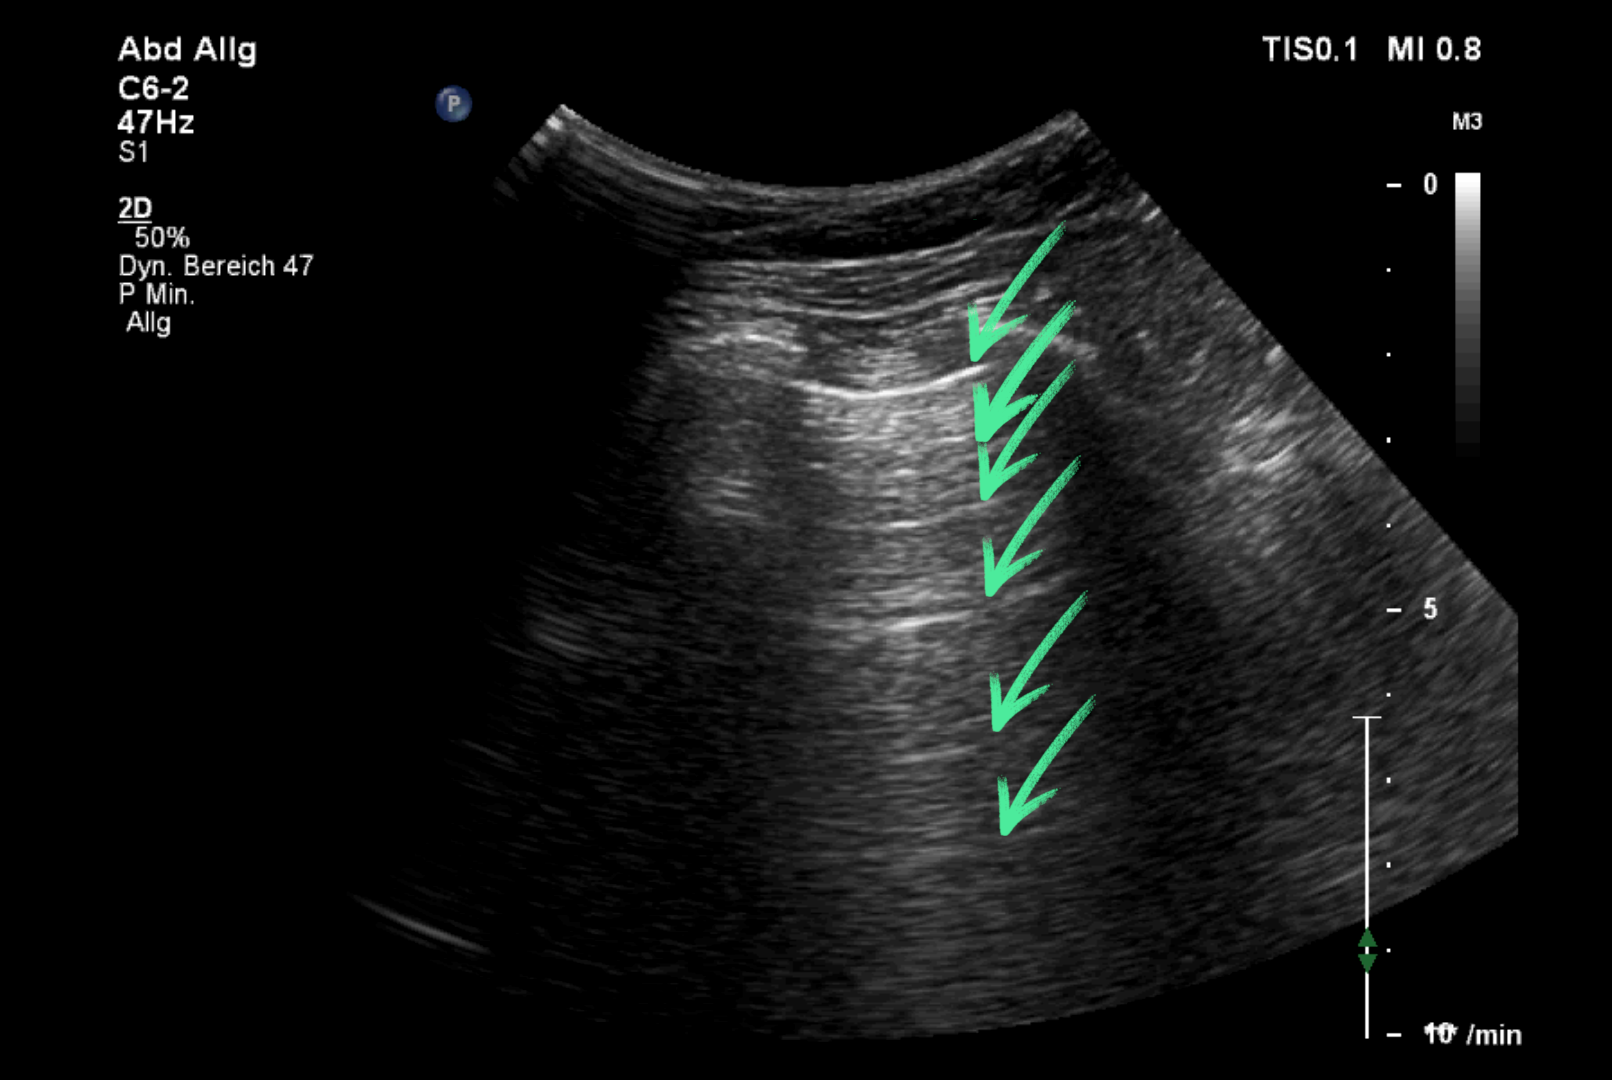

Reverberation

gleiche anatomische Struktur kommt mehrfach zur Darstellung